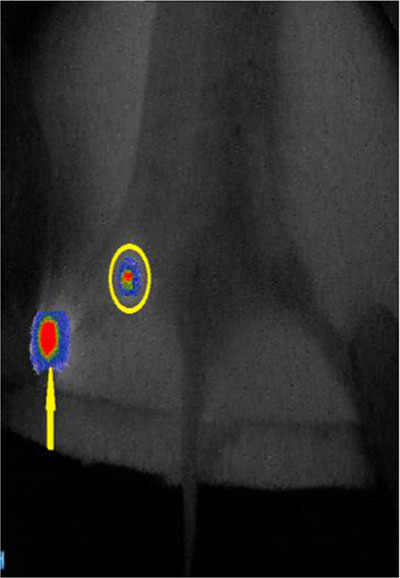

In the group of 5 μL injection dose, the visualization rate of SLN was 60% (6/10) after injection. Second-tier lymph node imaging was found in 50 μL (30%, 3/10) and 100 μL (90%, 9/10) injection dose one hour after injection (Figure 3). In the group of 10 μL injection dose, only SLN imaging was identified after 12 minutes (P < 0.05), and no other nodes or organs imaging were found (10/10, Figure 4A). The imaging of SLN was stable and clear for 20–24 hours in this group (Figure 4B). The results of SLN mapping and imaging showed in Table 1. After radiotracer injection, SLN imaging was identified by gamma probe after 2 minutes and no other nodes imaging were found after 18 hours (10/10). The location of SLN identified by the new tracer (10/10) was accorded with by the standard radiotracer (Figure 5).

Figure 5: The fusion image of the near-infrared fluorescence and the cyclone storage phosphor system. The location of SLN detected by the new tracer was consisted with the location of SLN detected by the radiotracer. (circle is SLN; yellow arrow is injection point).